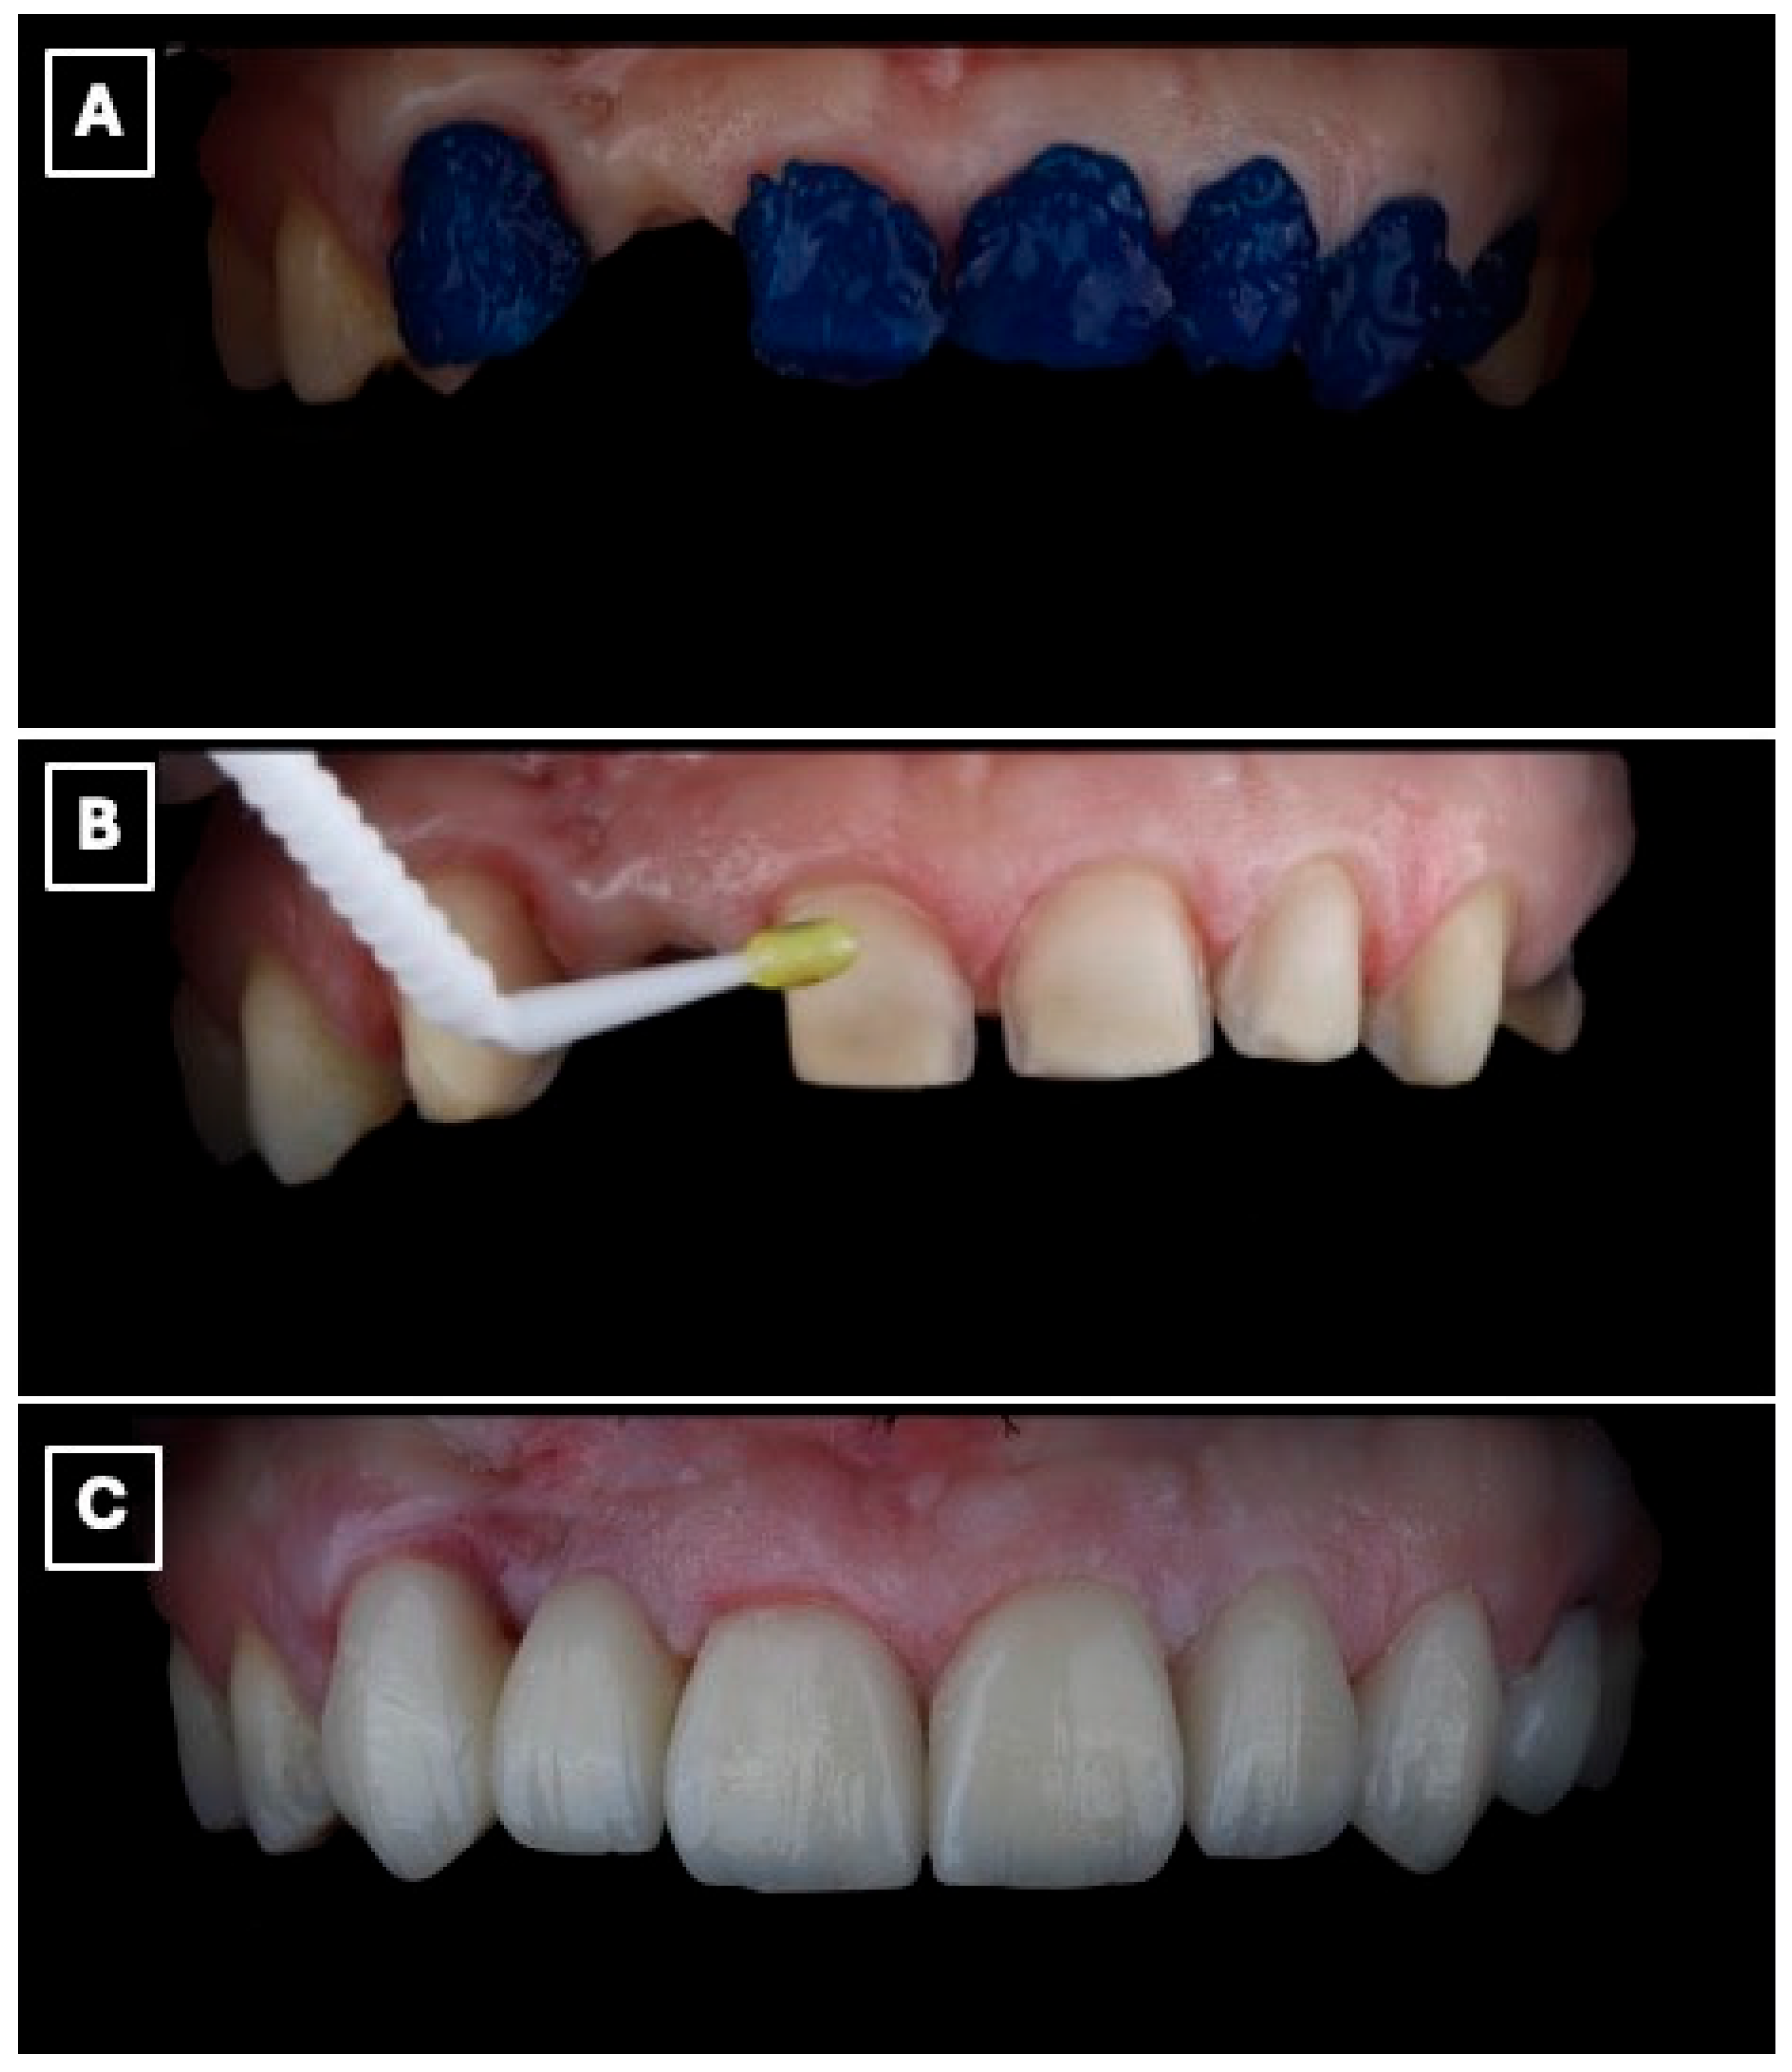

Figure 6.

Adhesive cementation of the lithium disilicate single-retainer cantilever resin-bonded fixed dental prosthesis using a light-cured resin cement. (A) Intraoral try-in and seating of the prosthesis prior to polymerization, confirming complete seating of the cantilever retainer, passive adaptation at the adhesive interface, and absence of premature contacts that could induce tensile or shear stresses. (B) Removal of excess resin cement during the gel phase following initial light activation, a critical step to prevent marginal overhangs, reduce plaque retention, and minimize the risk of gingival inflammation or marginal discoloration at the enamel-ceramic interface. (C) Final intraoral view after complete polymerization, demonstrating stable marginal adaptation, controlled occlusal scheme with elimination of functional contacts on the pontic, and harmonious esthetic integration of the restoration within the anterior smile zone, which are essential factors for long-term clinical success of cantilever resin-bonded prostheses.